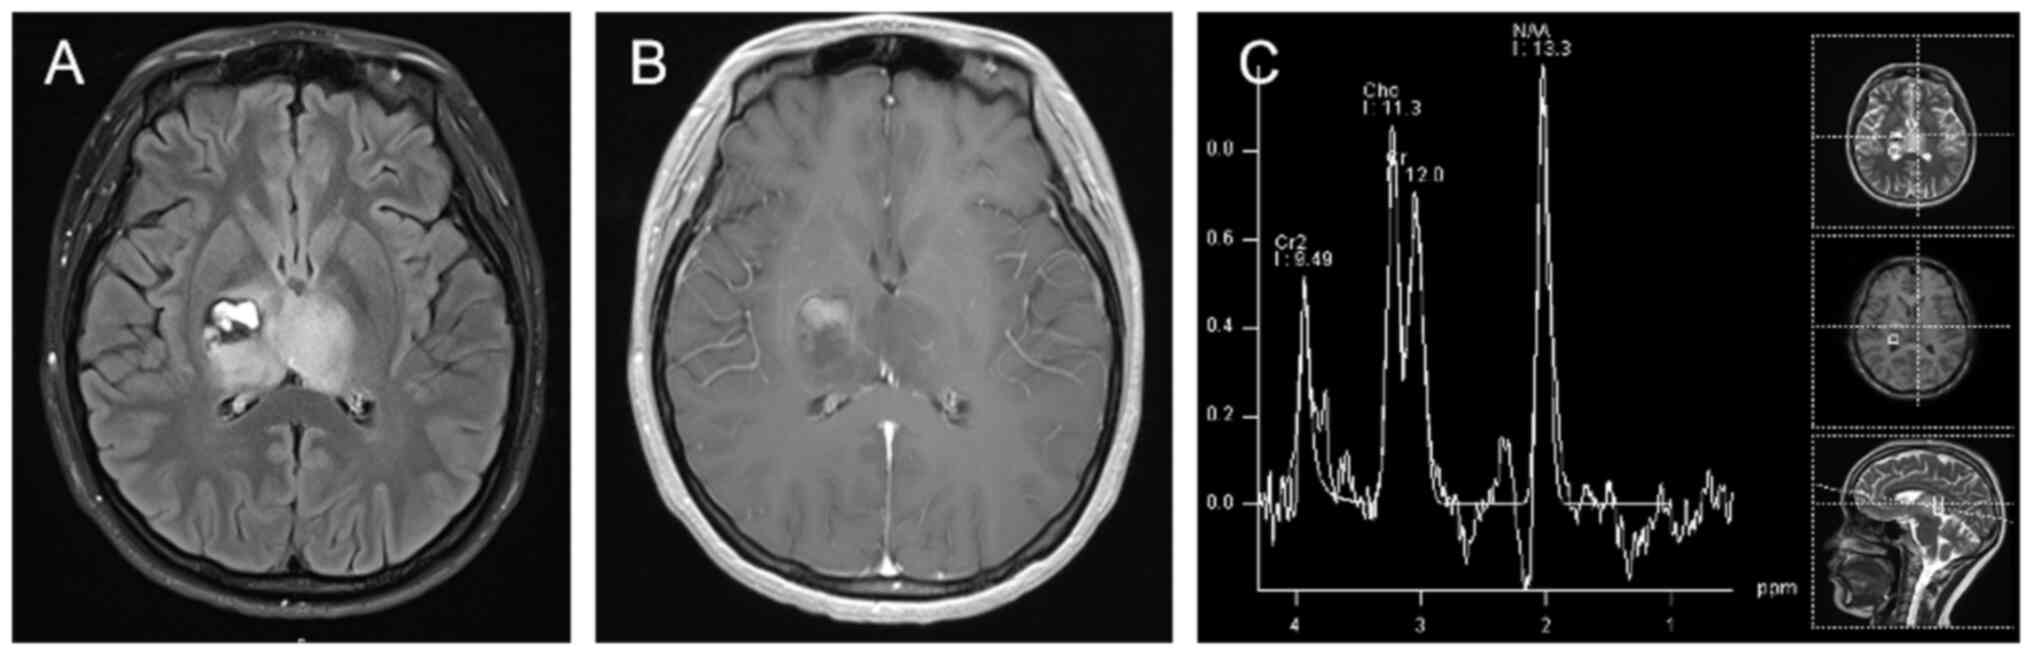

Personalized combination therapy for diffuse midline glioma: A case report

The present study aimed to analyze the efficacy of personalized combination therapy for patients with H3K27M mutant diffuse midline glioma (DMG) so as to explore new treatment options for further clinical research. The clinical data and prognosis of a patient with H3K27M mutant DMG are summarized and discussed in the context of the relevant literature. The patient was a 20‑year‑old female diagnosed with DMG treated with a combination of surgery, radiotherapy, chemotherapy, electric field therapy, immunotherapy and targeted therapy. An overall survival time of 28 months was achieved. In summary, personalized treatment strategies are expected to provide longer‑lasting survival benefits for patients with DMG.